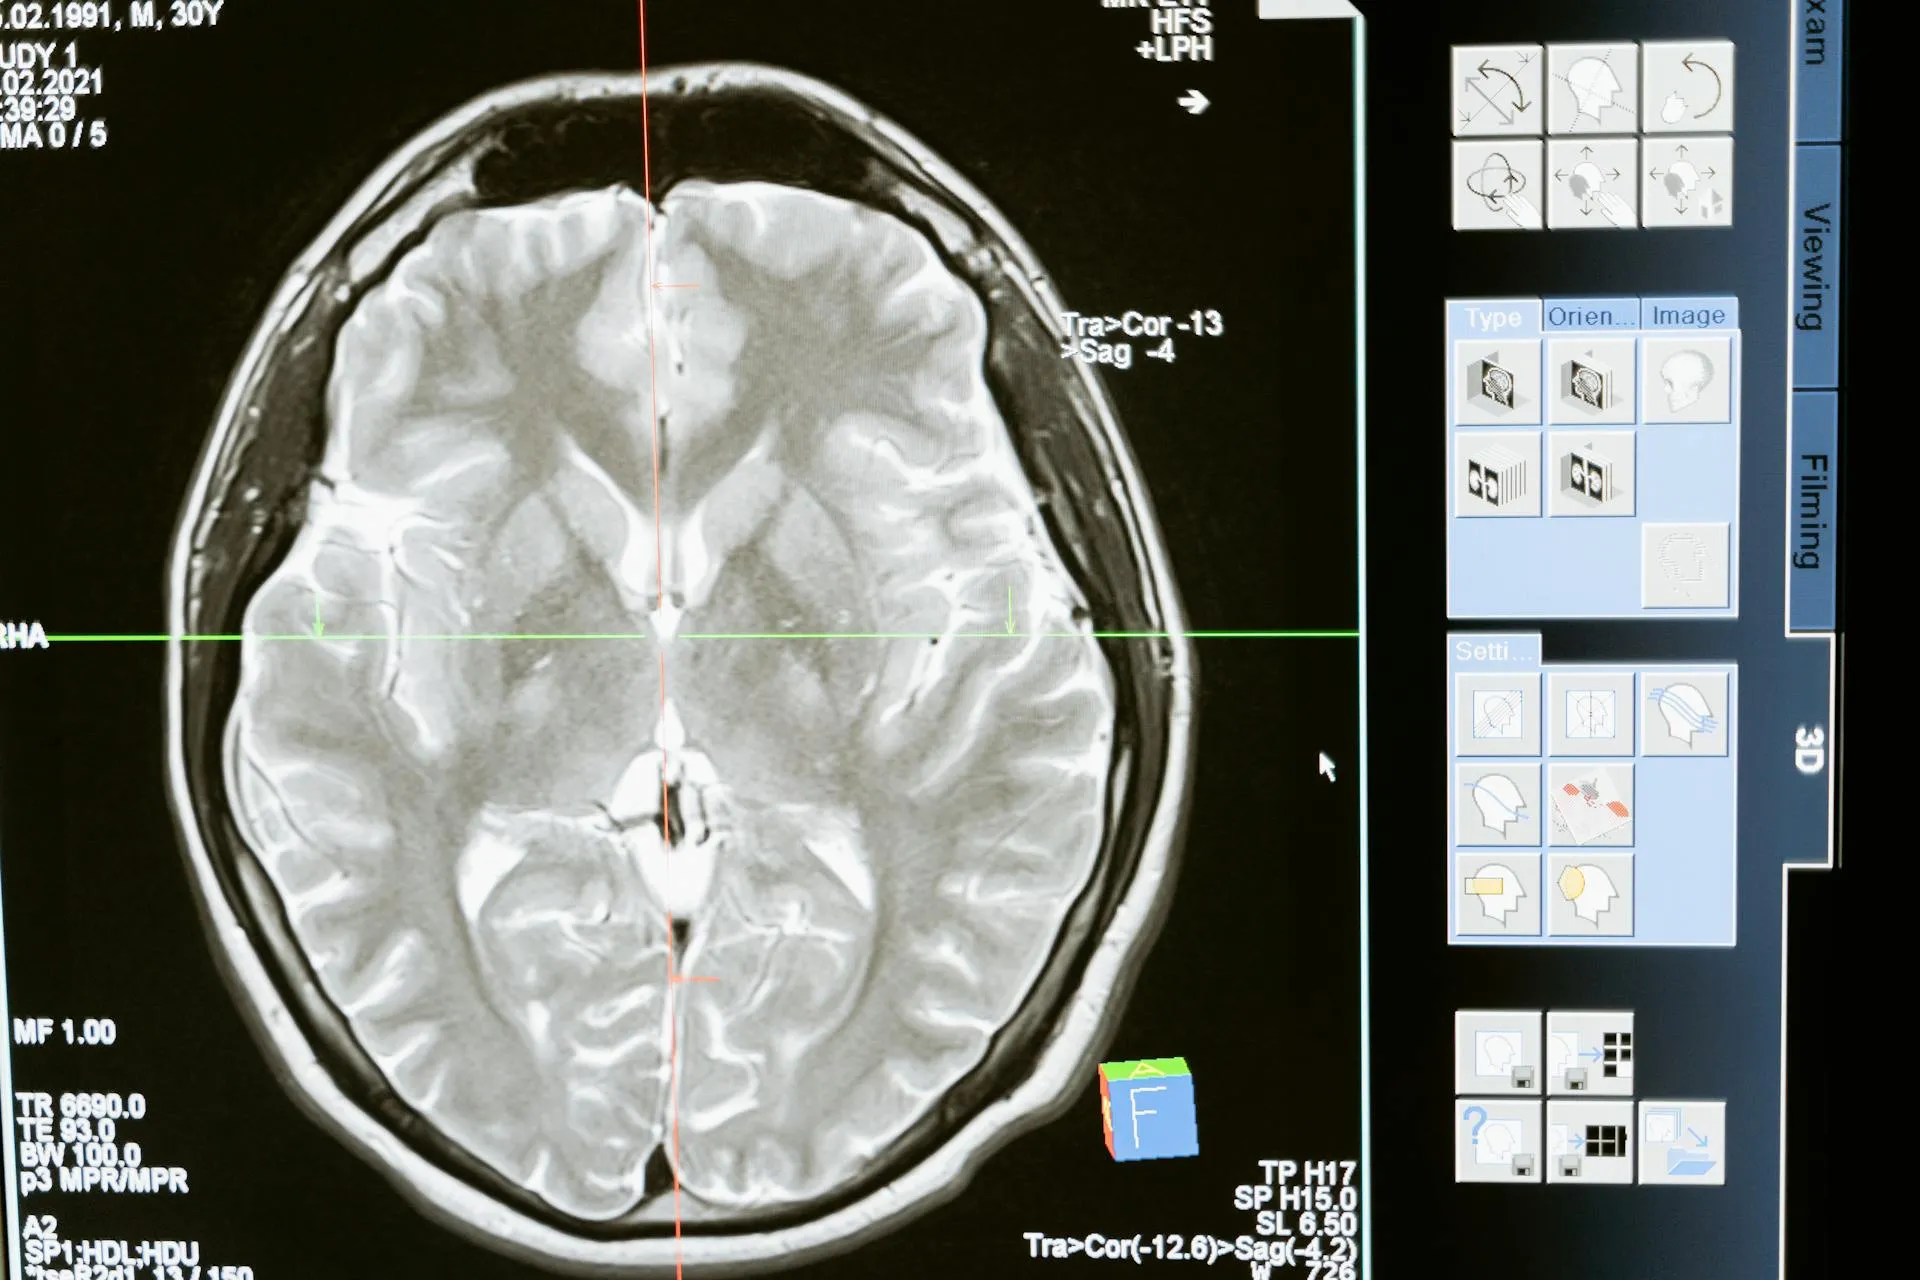

Udar mózgu to sytuacja, w której nagle dochodzi do przerwania dopływu krwi do mózgu lub do wylewu krwi w jego obrębie. To oznacza jedno: komórki nerwowe zaczynają obumierać. A ponieważ mózg to centrum dowodzenia całym organizmem, skutki udaru mogą dotknąć każdej funkcji ciała: ruchu, mowy, pamięci, a nawet świadomości.

Najczęściej mówimy o dwóch rodzajach udaru:

• Udar niedokrwienny – stanowi około 80% wszystkich przypadków. Dochodzi do niego, gdy naczynie krwionośne zaopatrujące mózg w tlen zostaje zablokowane, np. przez skrzep. Można to porównać do zakręcenia kranu, przez który woda nie może już płynąć, tylko że zamiast wody mówimy o życiodajnej krwi.

• Udar krwotoczny – rzadszy, ale często bardziej niebezpieczny. W tym przypadku dochodzi do pęknięcia naczynia krwionośnego i krwotoku do mózgu. Można to sobie wyobrazić jak pękniętą rurę wodociągową: krew rozlewa się tam, gdzie nie powinna, niszcząc delikatne struktury mózgu.